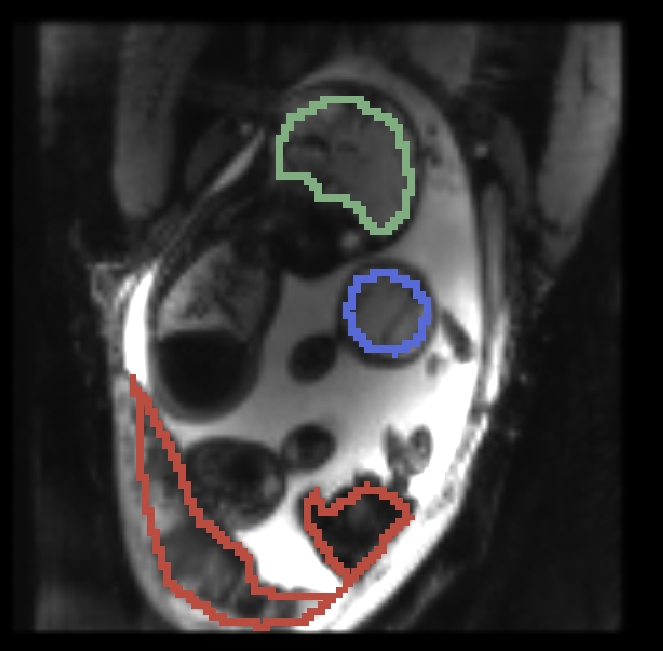

, manual segmentation on , manual segmentation on , propagated segmentation

Fig. 3 provides example results from the study for fetal brains and placentae. We observe that the reference frame is warped accurately by the temporal registration algorithm in the regions of fetal brains and placentae to represent the first frame in the series that is substantially different from the template. The delineations achieved by transferring manual segmentation labels from the reference frame to the coordinate system of the selected frame are in good alignment with the manual segmentation outlines for that selected frame.